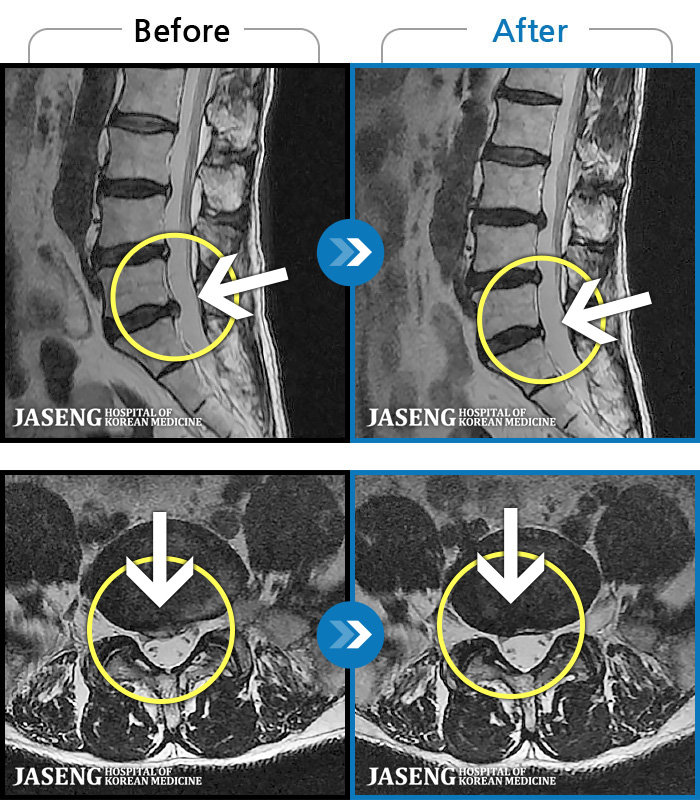

1,240 MRI ũ ʸ Ȯϼ.

ȯںп Ǹ ǿ ԿǾ, ο ġ ۿ Ƿ ġḦ Ͻñ ٶϴ.